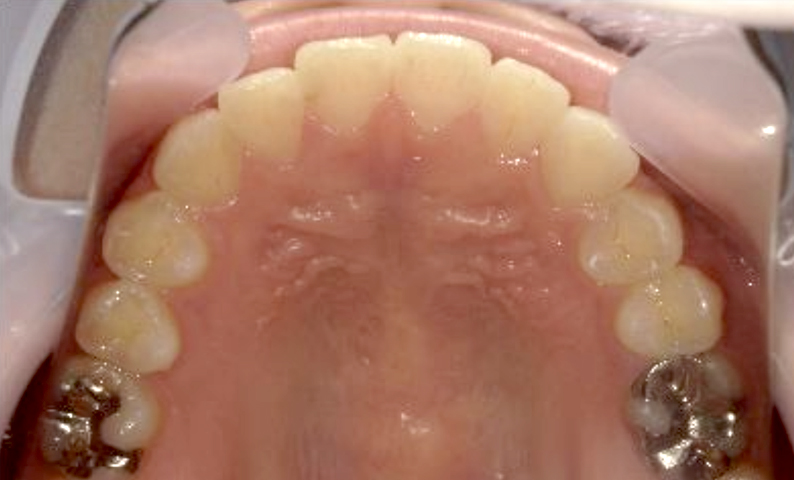

症例_024 上下顎の部分矯正

治療期間:13ヶ月金額:51万円+税女性前歯のガタガタ八重歯